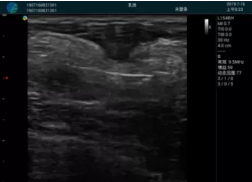

可視化甲狀腺穿刺引導(dǎo)

頸動脈血流充盈飽滿,無外溢

肝內(nèi)血管顯示清晰,血流敏感無外溢

病例二:

甲狀腺囊性結(jié)節(jié),囊壁鈣化,透聲好

甲狀腺囊性占位

2001年美國健康護(hù)理研究和質(zhì)量監(jiān)督局(AHRQ)批準(zhǔn)了一項(xiàng)關(guān)于提高患者安全性的報(bào)告,建議:在頸內(nèi)靜脈中心置管術(shù)時(shí)使用超聲引導(dǎo)。此后超聲引導(dǎo)穿刺被用于幾乎所有的急診穿刺操作,尤其是血管穿刺。

便攜超聲在急診穿刺中的應(yīng)用:

* 提高了穿刺成功率

* 減少了穿刺損傷及并發(fā)癥

* 縮短了操作時(shí)間

* 減輕了患者痛苦